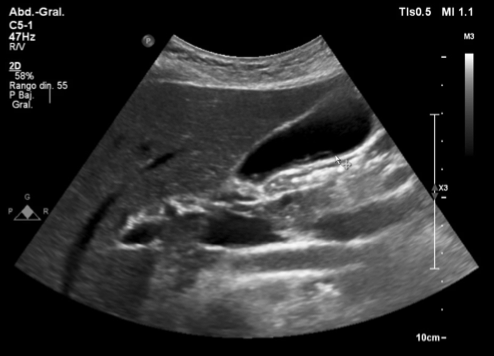

Hallazgos ecográficos

Hígado de tamaño, morfología y ecoestructura conservadas, con un quiste simple y sin alteraciones significativas en la vesícula, la vía biliar y el área pancreática. Tanto el bazo como los riñones sin hallazgos significativos. Sin embargo, se observan múltiples adenopatías en hilio hepático. Hallazgo inesperado que motiva la ampliación del estudio con gastroscopia y ecografía abdominal reglada preferentes.